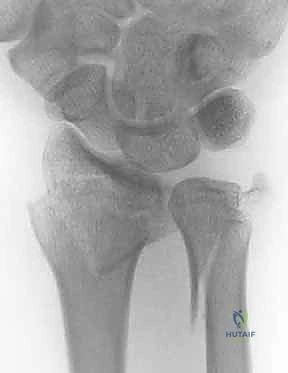

2. كسور رأس الزند (Ulnar Head Fractures)

رأس الزند هو الجزء المفصلي الدائري الذي يدور حوله الكعبرة.

* كسور مفصلية (Articular Fractures): تمتد خطوط الكسر لتشمل الغضروف المفصلي. إذا لم يتم إعادة العظام إلى وضعها التشريحي المثالي (Anatomic Reduction)، فإن المريض سيكون عرضة للإصابة بخشونة المفاصل المبكرة (Post-traumatic Osteoarthritis) وفقدان القدرة على تدوير الساعد.

* كسور غير مفصلية: تقع تحت السطح المفصلي مباشرة، ولكنها قد تؤدي إلى تشوه في زاوية رأس الزند.

صورة لكسر في رأس الزند

استخدام الأشعة السينية في التشخيص

1. الأشعة السينية (X-rays): بوضعيات متعددة (أمامية خلفية، وجانبية دقيقة). الوضعية الجانبية الحقيقية (True Lateral) حاسمة لاكتشاف أي خلع جزئي في المفصل (DRUJ).